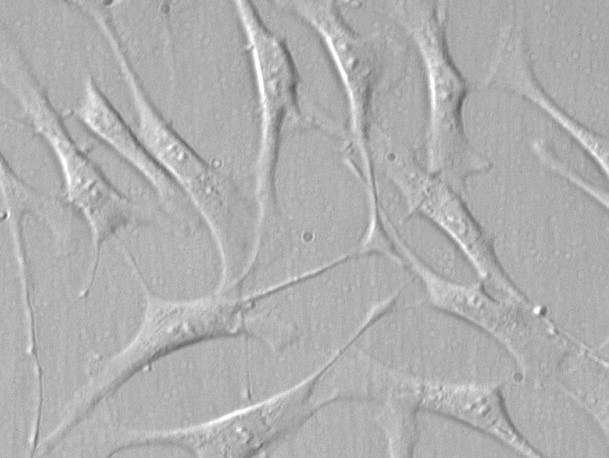

来自ScienCell研究实验室的HTMC分离自人眼的近关节和角膜巩膜区域。HTMC在P0冷冻保存并冷冻。每个小瓶含有>5×10^5个细胞,1ml体积。HTMC的特征在于具有对α-平滑肌肌动蛋白和纤连蛋白特异性的抗体的免疫荧光。HTMC对HIV-1,HBV,HCV,支原体,细菌,酵母和真菌均为阴性。在ScienCell研究实验室的条件下,HTMC保证进一步扩大15次人口倍增。​

小梁网位于虹膜根部周围,并有一条通向施莱姆管的狭缝,可将水管排入静脉血管。小梁网细胞(TMC)在房水流出中起积极作用,并且该途径是眼内压依赖性的。因此,TMC的损伤或死亡与开角型青光眼的发病机制有关[1]。TMC进一步表达神经递质和神经肽的受体,并对极低浓度的各种血管活性肽和生长因子作出反应,使这些细胞能够在多个水平上调节小梁网的通透性[2]。TMC培养为研究小梁网的功能控制提供了宝贵的工具,鼓励开发更有效的治疗青光眼的策略。​​